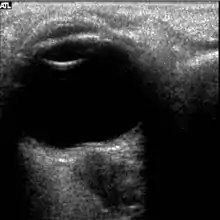

The first U.S. case of visual changes observed on orbit was reported by a long-duration astronaut that noticed a marked decrease in near-visual acuity throughout his mission on board the ISS, but at no time reported headaches, transient visual obscurations, pulsatile tinnitus or diplopia (double vision). His postflight fundus examination (Figure 1) revealed choroidal folds below the optic disc and a single cotton-wool spot in the inferior arcade of the right eye. The acquired choroidal folds gradually improved, but were still present 3 year postflight. The left eye examination was normal. There was no documented evidence of optic-disc edema in either eye. Brain MRI, lumbar puncture, and OCT were not performed preflight or postflight on this astronaut.[4]